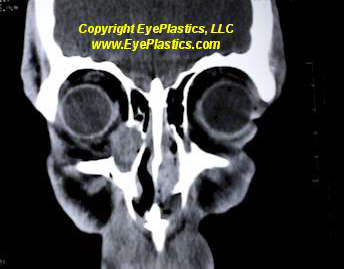

- CT scan detects an oval or round, homogenous mass with sharp margins, but falls short of a definitive diagnosis.

Imaging of Cavernous Hemangioma

- CT: smooth discrete lesion, fills with dye after 20 min; coronal cuts important to know tumor position relative to optic nerve. for sugical plan

- MRI: hypointense to fat on T1, hyperintense to fat on T2